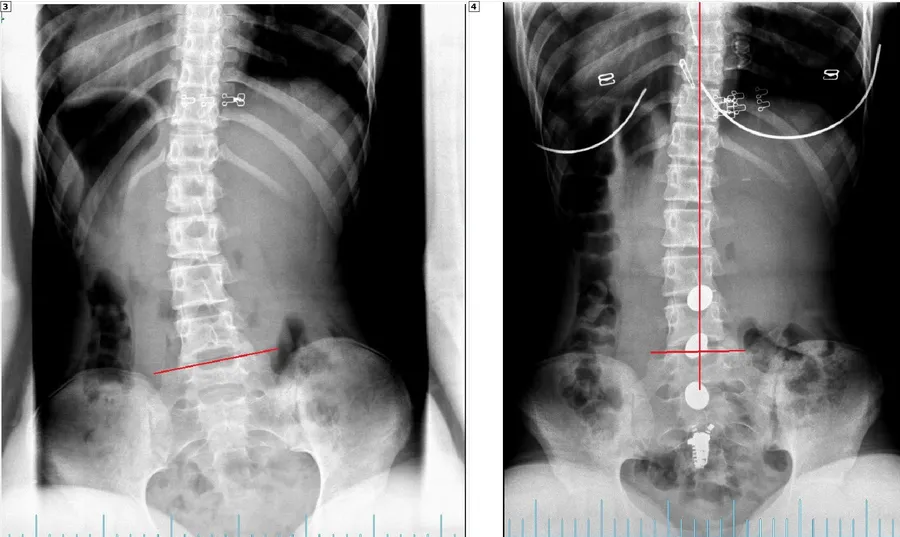

When the spine is well aligned, there is little to no nerve stress and the body is able to function optimally. Some times through physicals stresses such as motor vehicle accidents, slips and falls, sports injuries, and other traumas.  The spine can get misaligned and put pressure on the nervous system affecting the way that the body functions. Our job as doctors is to find out where the interference is and reduce it through Chiropractic Adjustments.  Objectively we can document where the problem is and then measure our patients progress as they go through the rehabilitation process.  Below is a series of before and after X-Rays of some our patients.

BEFORE AFTER

LUMBAR SCOLIOSIS CORRECTION